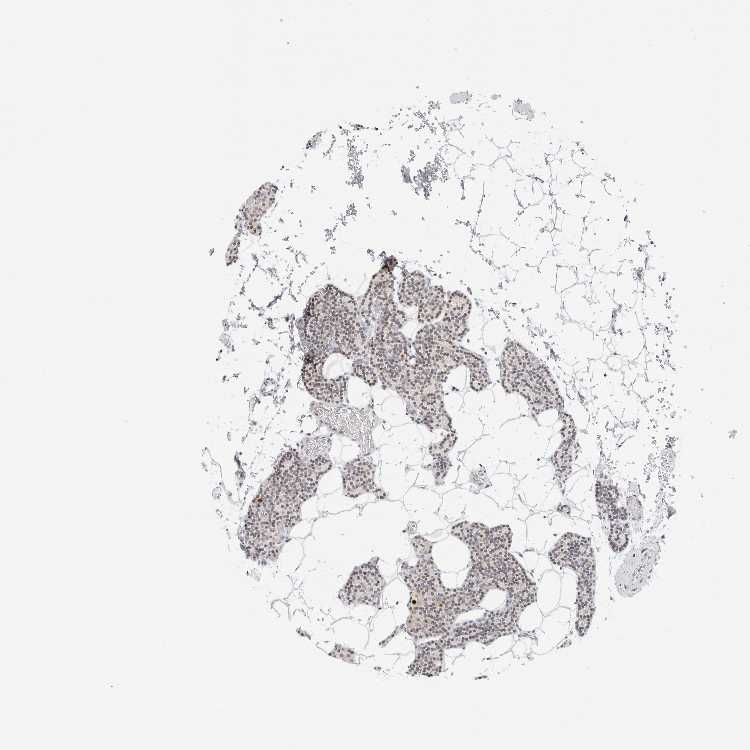

TISSUE PRIMARY DATA PARATHYROID GLAND Show tissue menu

Parathyroid gland

PARATHYROID GLAND - Expression summary

PARATHYROID GLAND - Antibody stainingi

Antibody staining in the annotated cell types in the current human tissue is reported as not detected, low, medium, or high, based on conventional immunohistochemistry profiling in selected tissues. This score is based on the combination of the staining intensity and fraction of stained cells.

Each image is clickable and will lead to virtual microscopy that enables deeper exploration of all samples and also displays staining intensity scores, fraction scores and subcellular localization as well as patient and tissue information for each sample.

Antibody HPA027120Antibody HPA027125Antibody HPA027268

Glandular cells MediumLowLow